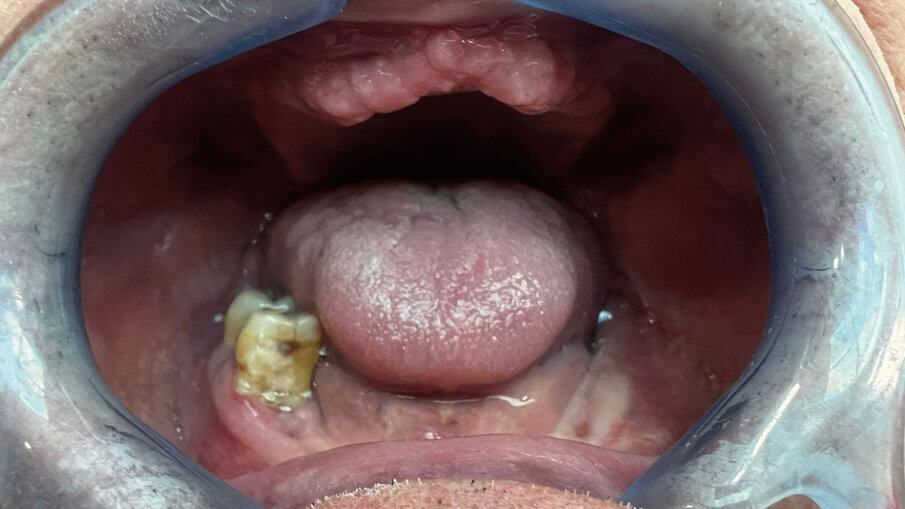

Fig. 4 - Foto della mucosa prima dell’inserimento del device.

Fig. 3 - RX iniziale. Il Paziente ottantenne si presenta con una protesi mobile realizzata e inserita da oltre 20 anni. Il desiderio di avere i denti fissi non l’ha mai abbandonato. Dalla RX si evince la chiara assenza totale di osso, situazione che non permette l’inserimento degli impianti in titanio tramite intervento tradizionale. Questo caso è stato affrontato tramite l’inserimento del Premaxillary Device.